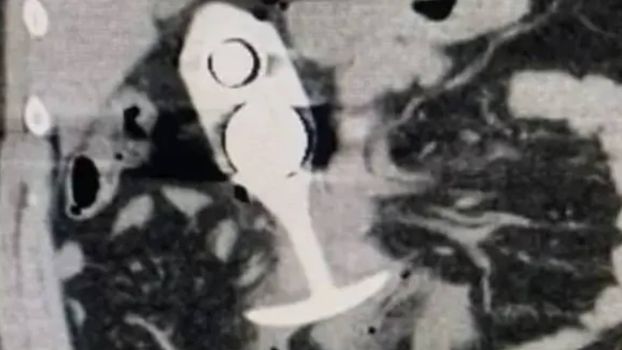

While the incident happened in April 2023, an image allegedly showing the patient’s scan following the event has recently begun circulating online, prompting warnings against wearing any metal objects during a scan.

A 23-year-old woman was left with horrific injuries after leaving a sex toy inserted during an MRI scan.

The unnamed woman had a silicone plug in her back passage while undergoing medical imaging and is said to have suffered a dangerous reaction with the scanner.

The woman didn’t realise that the sex toy she was using, which she thought was 100 per cent silicone, actually contained metal in its core.

It caused the item to be ‘dragged through her body’ causing the patient to ‘scream in pain’ a report filed with the U.S. Food and Drug Administration (FSA) stated.